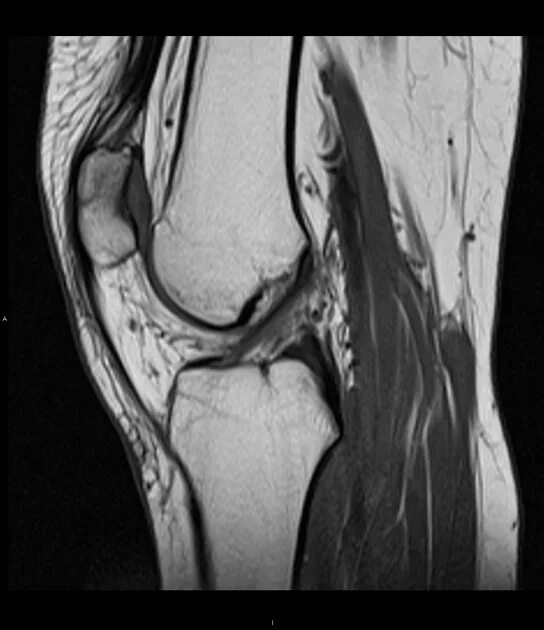

Повреждение хряща по outerbridge